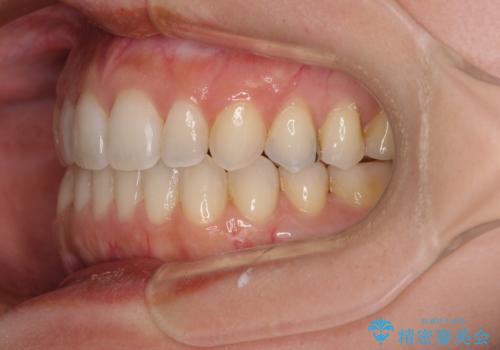

【モニター】狭い上顎歯列とオープンバイト 急速拡大装置を用いた矯正治療

- 前歯の開咬を気にして来院された患者様です。

上顎歯列が狭窄していたため、急速拡大装置により上顎骨を側方に拡大し、その後インビザラインにて矯正治療を行うこととしました。

舌の突出癖が開咬の原因であったので、改善のための舌トレーニングを行っていただきました。

舌トレーニングは後戻りにも大きく影響するため、とても重要なトレーニングです。